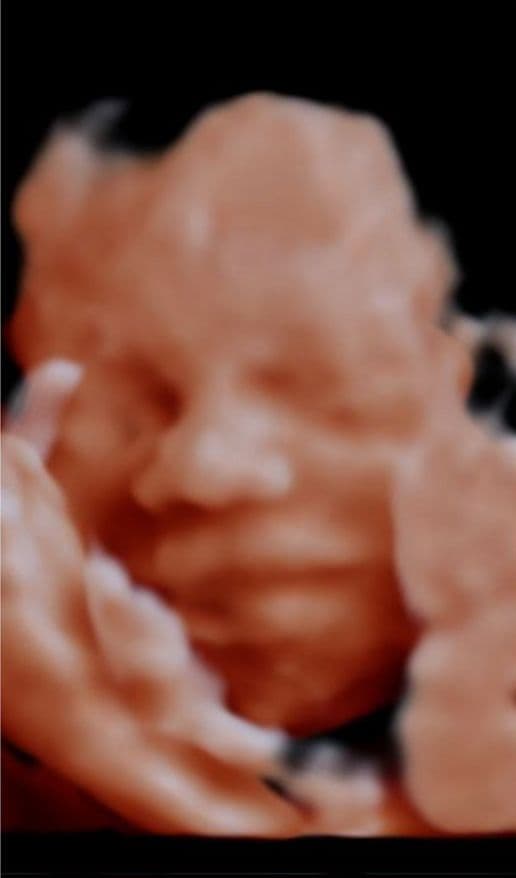

See babies, before & after

Your baby

See your baby smile in 2 minutes.